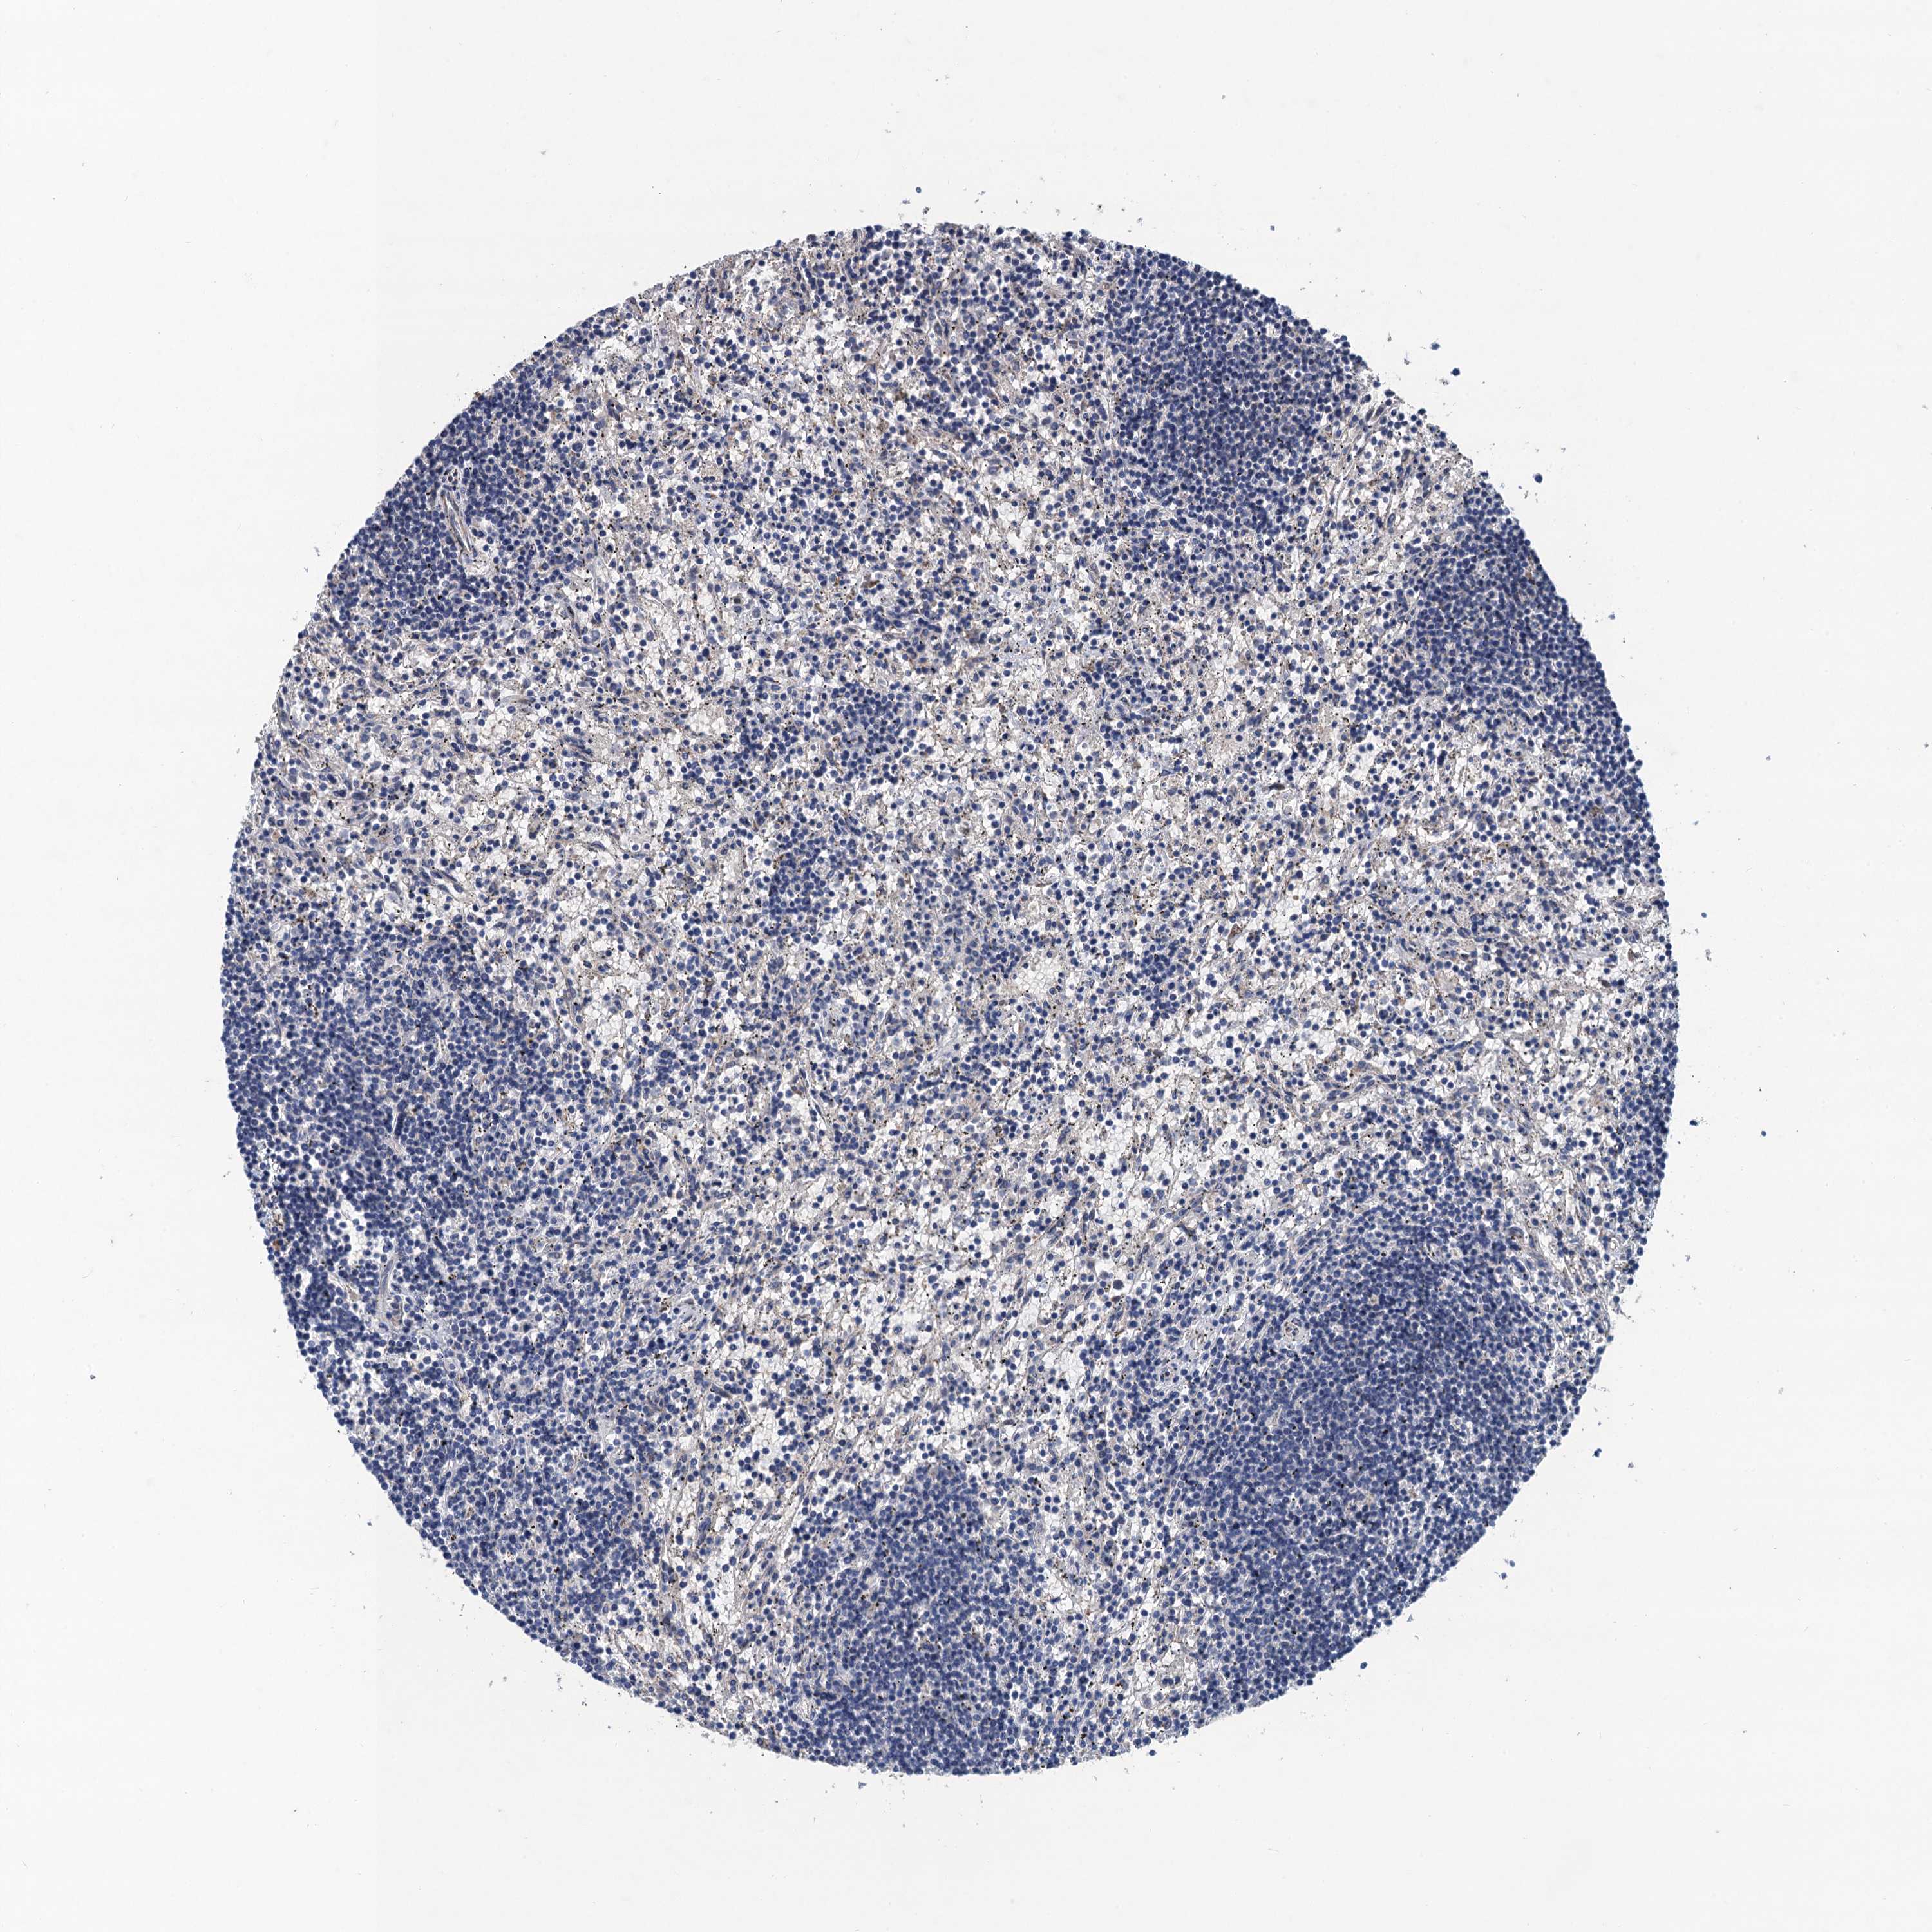

CANCER LYMPHOMA Show tissue menu

LYMPHOMA - Protein expressioni

A mouse-over function shows sample information and annotation data. Click on an image to view it in a full screen mode. Samples can be filtered based on level of antibody staining by selecting one or several of the following categories: high, medium, low and not detected. The assay and annotation is described here.

Each image is clickable and will lead to virtual microscopy that enables deeper exploration of all samples and also displays staining intensity scores, fraction scores and subcellular localization as well as patient and tissue information for each sample.

Antibody HPA041229

Staining

High

Medium

Low

Not detected

Intensity

Strong

Moderate

Weak

Negative

Quantity

>75%

75%-25%

<25%

None

Location

Nuclear

Cytoplasmic/membranous

Cytoplasmic/membranous,nuclear

Hodgkin's disease, NOS

Malignant lymphoma, non-Hodgkin's type, High grade

Malignant lymphoma, non-Hodgkin's type, Low grade